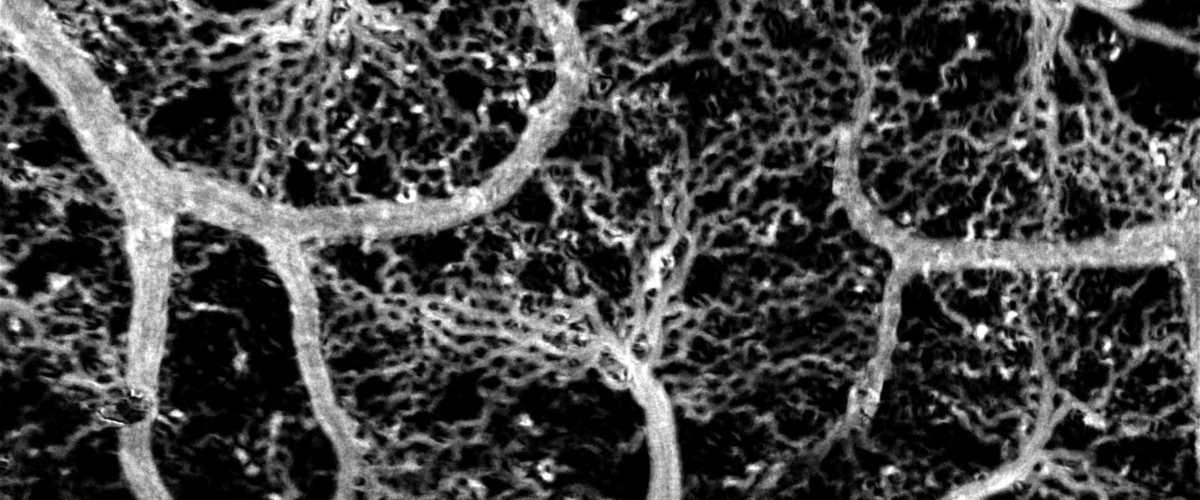

Такой подход позволил идентифицировать отдельно движущиеся эритроциты и получать детальные изображения вплоть до мельчайших капилляров.

Тестирование на моделях животных показало, что даже в сложных случаях при визуализации труднодоступных сосудов, где не видно движений отдельных эритроцитов, удается картировать кровеносные сети.